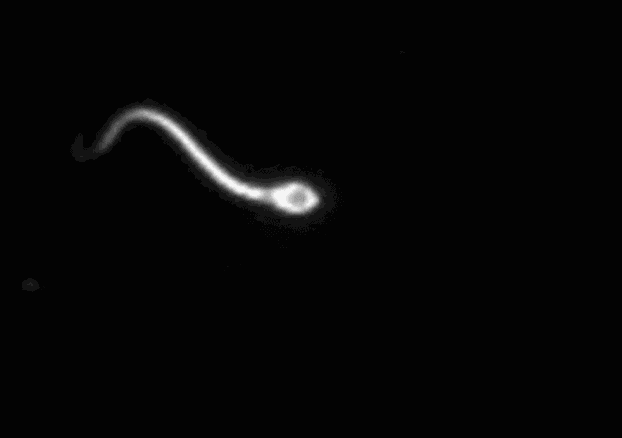

畸形精子症也就是指精液中正常形态的精子比例过低,通俗来讲就是精子“长相”不合格的太多。

根据世界卫生组织(WHO)的标准,经过严格形态学评估,正常形态精子比例低于4%即为畸形精子症。这些精子可能在头部(过大、过小、双头)、颈部(弯曲)或尾部(双尾、卷尾)存在各种奇形怪状。

这些形态异常的精子,难以穿透卵子外层坚硬的透明带,即便能接近卵子,也很难成功完成受精过程,进而拖慢备孕进度,增加受孕失败的概率。